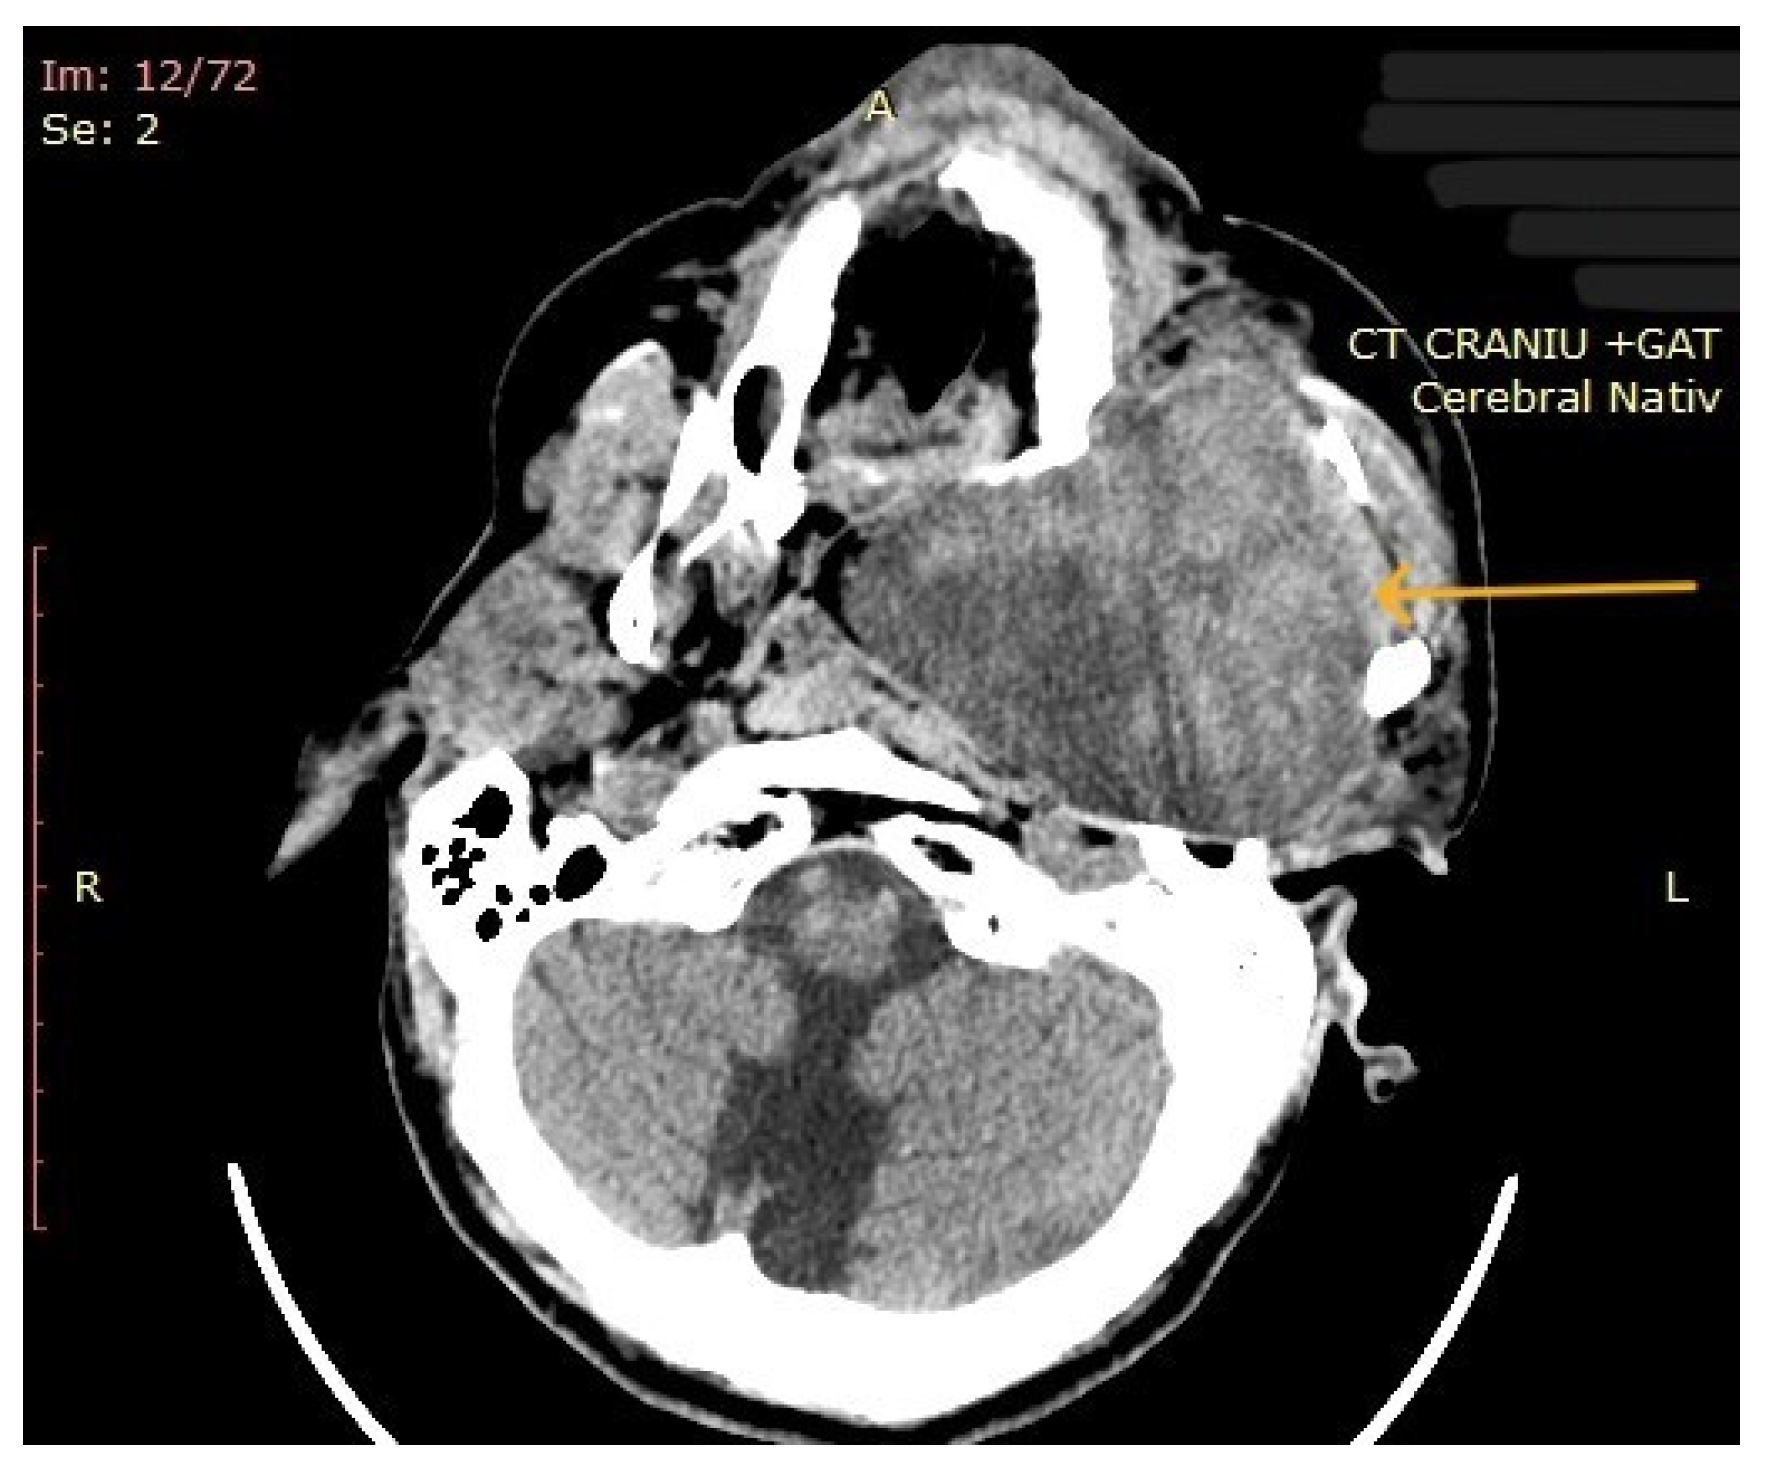

3.2. Imaging Aspects

| 10 | Left parapharyngeal region with maxillary and intracranial extension | Discomfort in breathing, chewing, swallowing, phonation, sleeping, regional pain, fatigue | 5 years | 10 cm | Benign tumor of soft tissue |